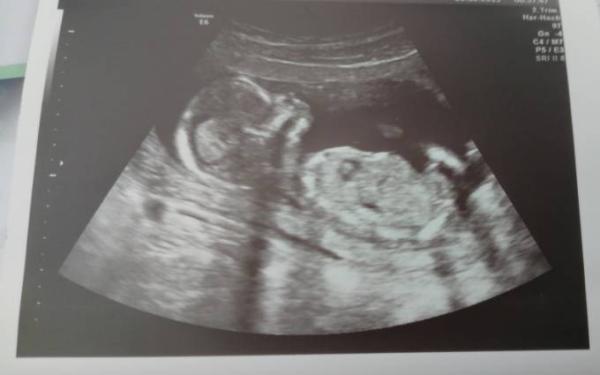

Guten Morgen, War gestern bei 14+4 bei meinem Vorsorgetermin. Dem Baby geht es gut und ansonsten passt auch alles. Schwangerschsftsbeschwerden sind so gut wie alle weg. Zugenommen habe ich jetzt doch mal 1,8 Kilo seit Anfang der Ss und so langsam sieht man auch was :) Leider hat mir meine Frauenärztin gesagt, dass sie ab Ende des Jahres in eine andere Praxis geht. 40 km entfernt :( jetzt weiß ich nicht was ich tun soll, die einzige die ich noch mag in der Praxis hat sogut wie nie Zeit und ansonsten mag ich dort keinen :( ich war gestern so fertig deswegen, ich glaub ich muss dort nochmal anrufen und das klären, weil die wollen mich irgendjemanden geben, bzw. Mehrere Ärzte, das verkrafte ich nicht mitten in der Ss ich weiß aber gar nicht wie ich das formulieren soll, dass es nicht rüber kommt als wäre ich zu weinerlich oder wütend darüber? Ach man :( Dafür war meine Ärztin gestern wieder total lieb. Und nachdem ich gefragt habe, was es denn werden könnte, hat sie sich mit dem Ultraschall soviel Zeit gelassen und dann auch nochmal alles abgemessen. Leider war mein kleiner Fratz so zappelig gewesen und hat die Beine verschränkt, dass man nicht wirklich was sehen konnte und die Ärztin dann nicht sicher war. Wir haben dann zusammen bestimmt, dass wir dann doch das nächste Mal schauen, wenn mein Freund dabei ist :)

Foto vergessen

Aber du hast ein ganz tolles Bild bekommen!!!

Ja Danke :) und meine Ärztin ist auch sowas von toll, sie wartet auch immer ab um ein tolles bild zu bekommen. aber ich befürchte, dass ich sie die letzten Monate vor der Geburt leider nicht mehr sehen werde :(